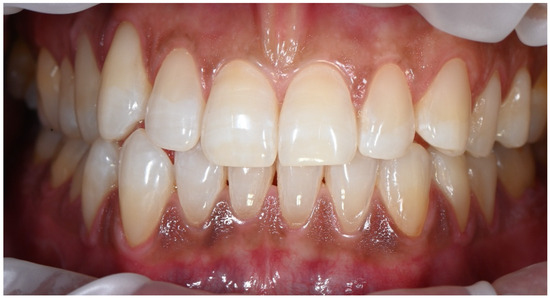

Clinical Management of Cervical Restorations with Closing Gap Technique: A Follow-Up of Two Cases

Background: Cervical restorations remain clinically challenging due to complex anatomy, limited enamel availability, and difficulties in achieving reliable adhesion at dentin or cementum margins. Polymerization shrinkage and marginal leakage are frequent causes of failure. Although the Closing Gap Technique has been proposed to [...] Read more.

Background: Cervical restorations remain clinically challenging due to complex anatomy, limited enamel availability, and difficulties in achieving reliable adhesion at dentin or cementum margins. Polymerization shrinkage and marginal leakage are frequent causes of failure. Although the Closing Gap Technique has been proposed to improve marginal adaptation in cervical restorations, evidence supporting its medium- to long-term clinical performance is limited. The aim of this case report was to evaluate the clinical effectiveness of the Closing Gap Technique in the restoration of carious and non-carious cervical lesions. Materials and Methods: Two patients presenting with cervical lesions were treated using the Closing Gap Technique. One case involved carious cervical lesions, while the second included multiple non-carious cervical lesions. Restorations were performed following an enamel-anchored incremental layering protocol with resin composite. Clinical evaluations were conducted at 8 years (case #1) and 2 years (case #2) post-treatment, respectively. Results: Both cases demonstrated favorable clinical outcomes at follow-up. The restorations exhibited good marginal integrity, satisfactory esthetics, absence of marginal discoloration, no secondary caries, and no signs of debonding. The only minor defect observed was slight chipping of one of the restorations. Conclusions: Within the limitations of this case report, the Closing Gap Technique showed stable and predictable medium- and long-term clinical performance, supporting its use as a viable restorative approach for managing cervical lesions in daily clinical practice. Full article